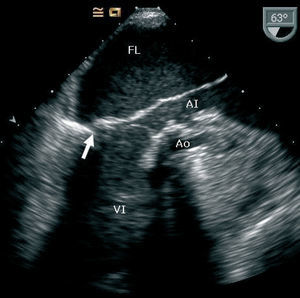

Al no haber correlación entre el ecocardiograma transtorácico y la situación clínica, se realiza un ecocardiograma transesofágico que revela una falsa cámara en el interior de la aurícula izquierda formada por la pared auricular posterior disecada, y que ocupa casi la totalidad del verdadero lumen (fig. 1). Se observa también flujo sistólico retrógrado en su interior proveniente de la pared posterior del ventrículo izquierdo por debajo de la prótesis. No se evidencia comunicación entre el verdadero y el falso lumen ni regurgitación perivalvular (fig. 2).

Fig. 1.